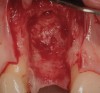

A 53-year-old woman presented with a failing implant in the No. 7 site (Figure 12 and Figure 13). Her desire was to eliminate infection and preserve esthetics. A team effort between the periodontist and restorative dentist to advocate for additional restorative dentistry as well as manage the patient’s expectation of time required was essential. In addition, the patient needed to have realistic expectations of a compromised outcome. Both the restorative dentist and the periodontist informed the patient about the difficulty of achieving this with acceptable esthetic results. Mutual emotional and technical support was required to successfully complete this case, from initial grafting of the defect to placement of anterior restorations (Figure 14 through Figure 23).